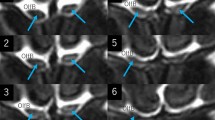

On axial T2-weighted MRI performed in the initial examination, the central part of some intraorbital ONs was delineated as a well-demarcated linear hyperintense area (Fig. 2). The finding was identified in 17 of 89 patients (19%), 9 on the right side and 11 on the left side. On the thin-sliced serial coronal images, hyperintense areas were identified on both sides in 81 patients (91%). They were delineated as continuous hyperintense areas in the ONs with an inconsistent appearance even in the same nerve, from the orbital apex to its tip. In 11 patients (12.4%), the areas were divided into upper and lower parts by a horizontal septum, 9 on the right and 10 on the left. Other patients had hyperintense areas in the ONs with variable morphologies, lacking a septum (Fig. 3). These areas involved the central part of the ON and showed highly interindividual variability (Fig. 4). Furthermore, on the thin-sliced sagittal images, hyperintense areas were identified in 41 patients (46%), 30 on the right and 28 on the left, in variable parts of the intraorbital ONs (Fig. 5).

a–h Serial coronal T2-weighted magnetic resonance images of a patient showing continuous but inconsistent hyperintense areas in the intraorbital optic nerve that distribute from the orbital apex to the posterior pole of the eyeball. Note that, in some images, the areas are divided into upper and lower parts by a horizontal septum, while others show variable morphologies, lacking a septum. Arrow: optic nerve; dotted arrow: optic sheath

a–f Coronal T2-weighted magnetic resonance images of different patients showing hyperintense areas variably distributing in the intraorbital optic nerves. In a–c, the optic nerve is variably divided into upper and lower parts by a horizontal septum, while such septum is not found in d–f FL frontal lobe, IRM inferior rectus muscle, LRM lateral rectus muscle, MRM medial rectus muscle, SRM superior rectus muscle a–c right orbit; d–f left orbit; arrow optic: nerve; dotted arrow: optic sheath